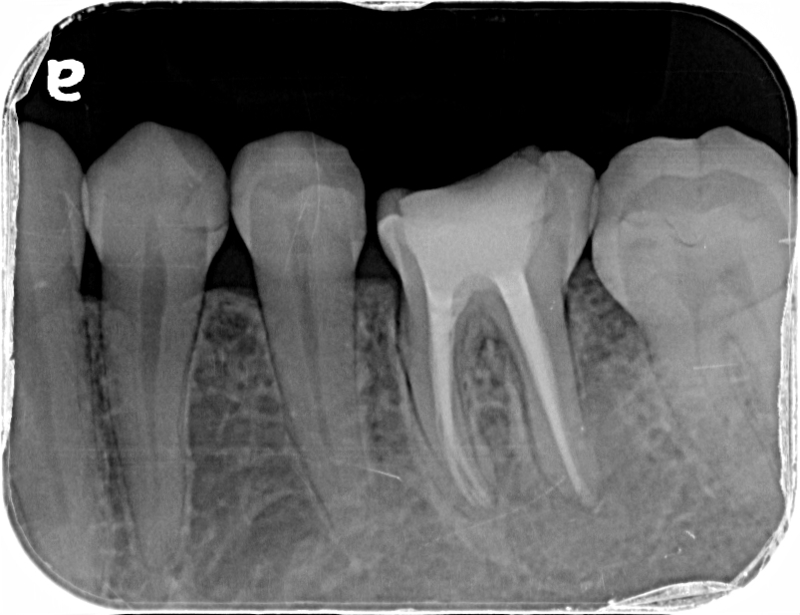

術前のレントゲン写真です。

根管治療後のレントゲン写真です。